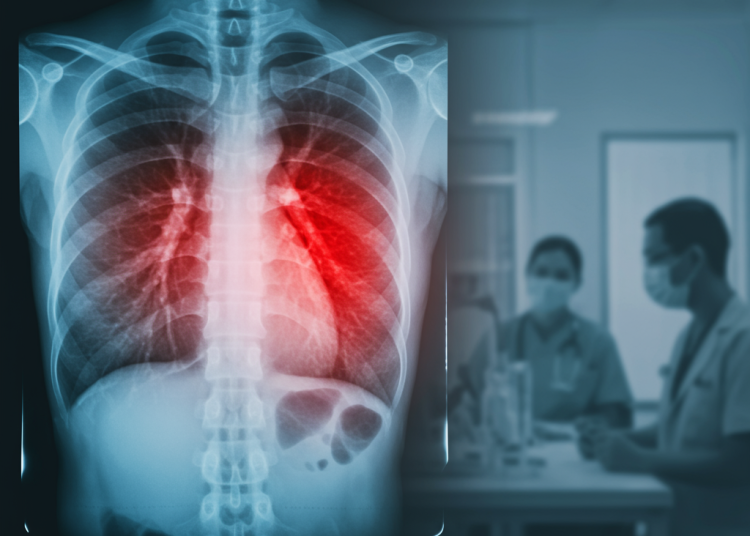

Untuk mendiagnosis pneumonia, tenaga medis akan melakukan pemeriksaan fisik, tes darah, serta pencitraan dada seperti rontgen. Dalam beberapa kasus, pemeriksaan lebih lanjut seperti CT scan dada atau bronkoskopi mungkin diperlukan untuk menentukan tingkat keparahan atau mengidentifikasi penyebab yang kurang umum.